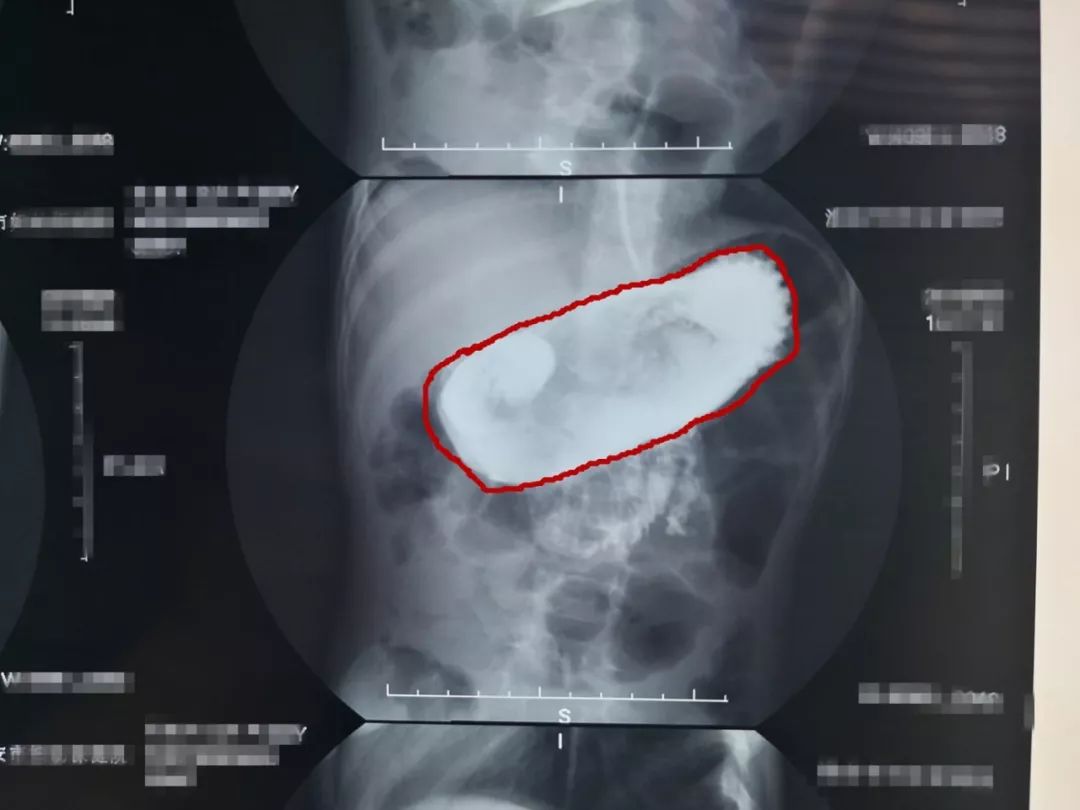

医生为盼盼做了上消化道造影

发现她胃内有一块明显异物

图 检查显示,盼盼胃内有异物